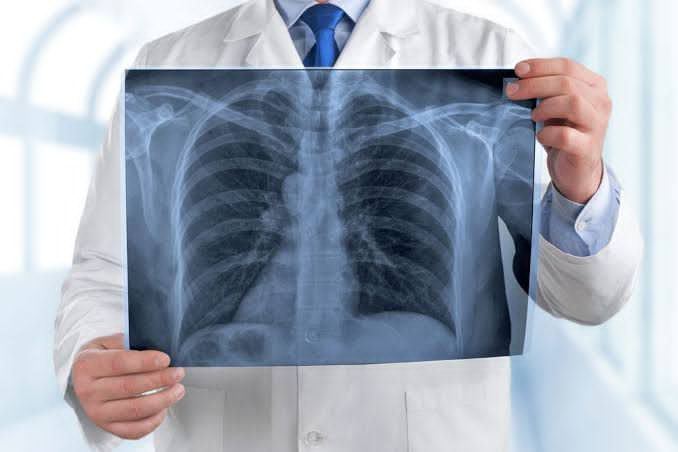

El director del Hospital General de Zona (HGZ) No. 36, doctor Venancio Matacapan Flores, explicó que la neumonía es una infección respiratoria aguda que afecta los pulmones y puede ser causada por bacterias, virus o hongos, que ocasionan que los alvéolos, que son los pequeños sacos donde se realiza el intercambio de oxígeno, se llenen de pus o líquido, lo que provoca dificultad para respirar y puede comprometer seriamente la salud del paciente.

Detalló que, los principales síntomas son: fiebre, tos con flema, dolor en el pecho, escalofríos, respiración rápida o dificultad para respirar, así como debilidad o cansancio generalizado, donde las personas con enfermedades crónico-degenerativas como: diabetes, hipertensión, asma o enfermedad pulmonar obstructiva crónica (EPOC), así como los adultos mayores y los niños pequeños, son los grupos más vulnerables.